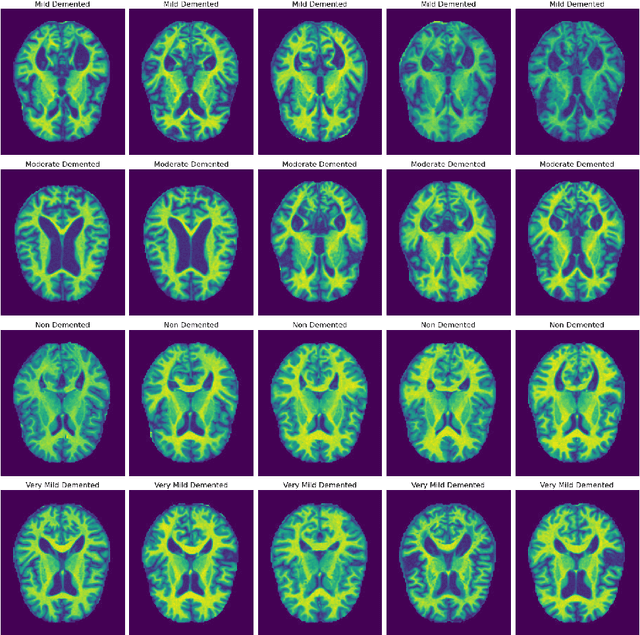

Abstract:Alzheimer's disease (AD) represents the primary form of neurodegeneration, impacting millions of individuals each year and causing progressive cognitive decline. Accurately diagnosing and classifying AD using neuroimaging data presents ongoing challenges in medicine, necessitating advanced interventions that will enhance treatment measures. In this research, we introduce a dual attention enhanced deep learning (DL) framework for classifying AD from neuroimaging data. Combined spatial and self-attention mechanisms play a vital role in emphasizing focus on neurofibrillary tangles and amyloid plaques from the MRI images, which are difficult to discern with regular imaging techniques. Results demonstrate that our model yielded remarkable performance in comparison to existing state of the art (SOTA) convolutional neural networks (CNNs), with an accuracy of 99.1%. Moreover, it recorded remarkable metrics, with an F1-Score of 99.31%, a precision of 99.24%, and a recall of 99.5%. These results highlight the promise of cutting edge DL methods in medical diagnostics, contributing to highly reliable and more efficient healthcare solutions.